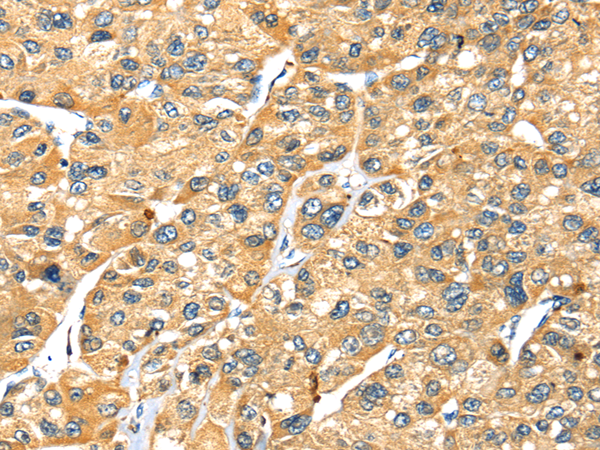

分类: 科研抗体货号: P08826别名:应用: IHC反应种属: Human, Mouse, Rat